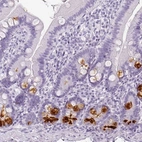

Immunohistochemistry analysis in human small intestine and skeletal muscle tissues using HPA048334 antibody. Corresponding REG3A RNA-seq data are presented for the same tissues.